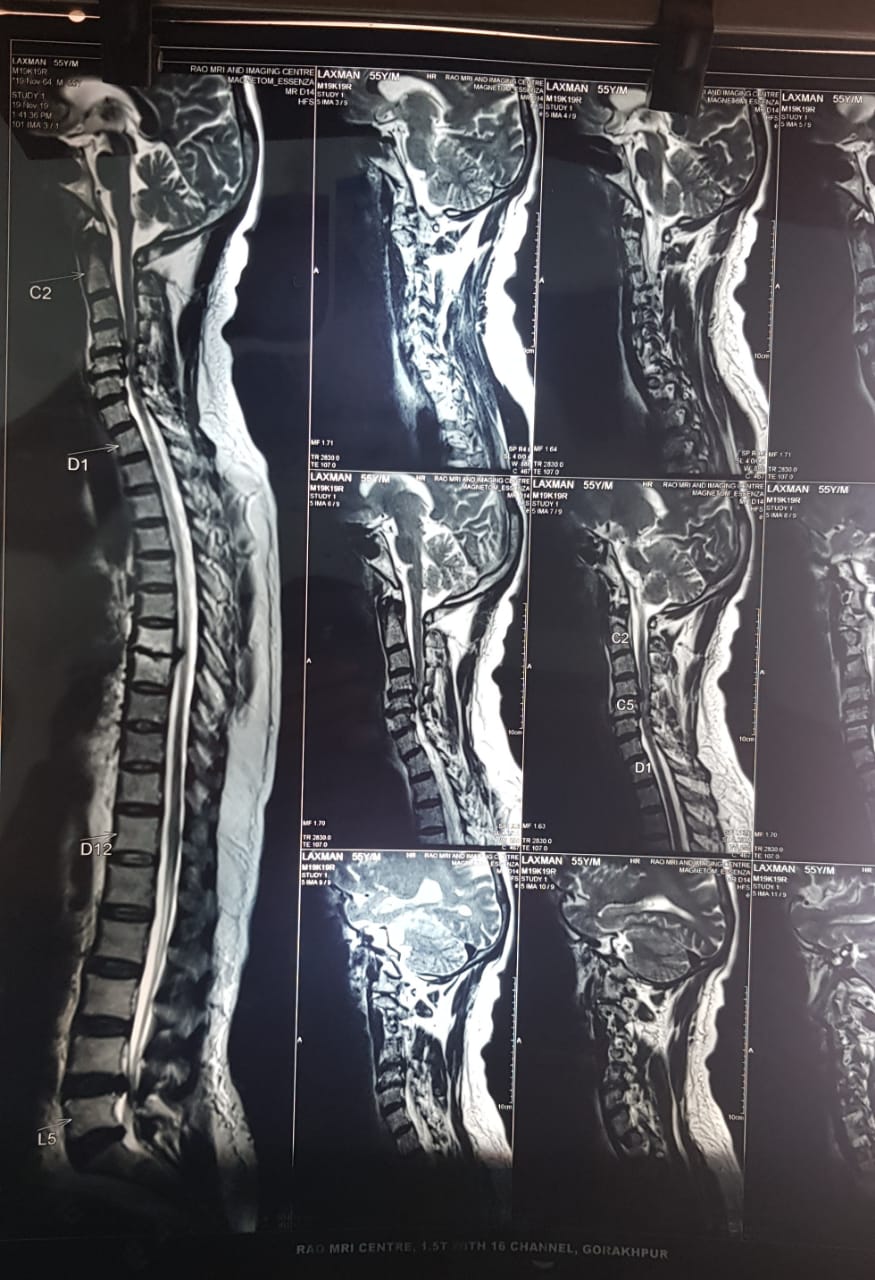

Cases